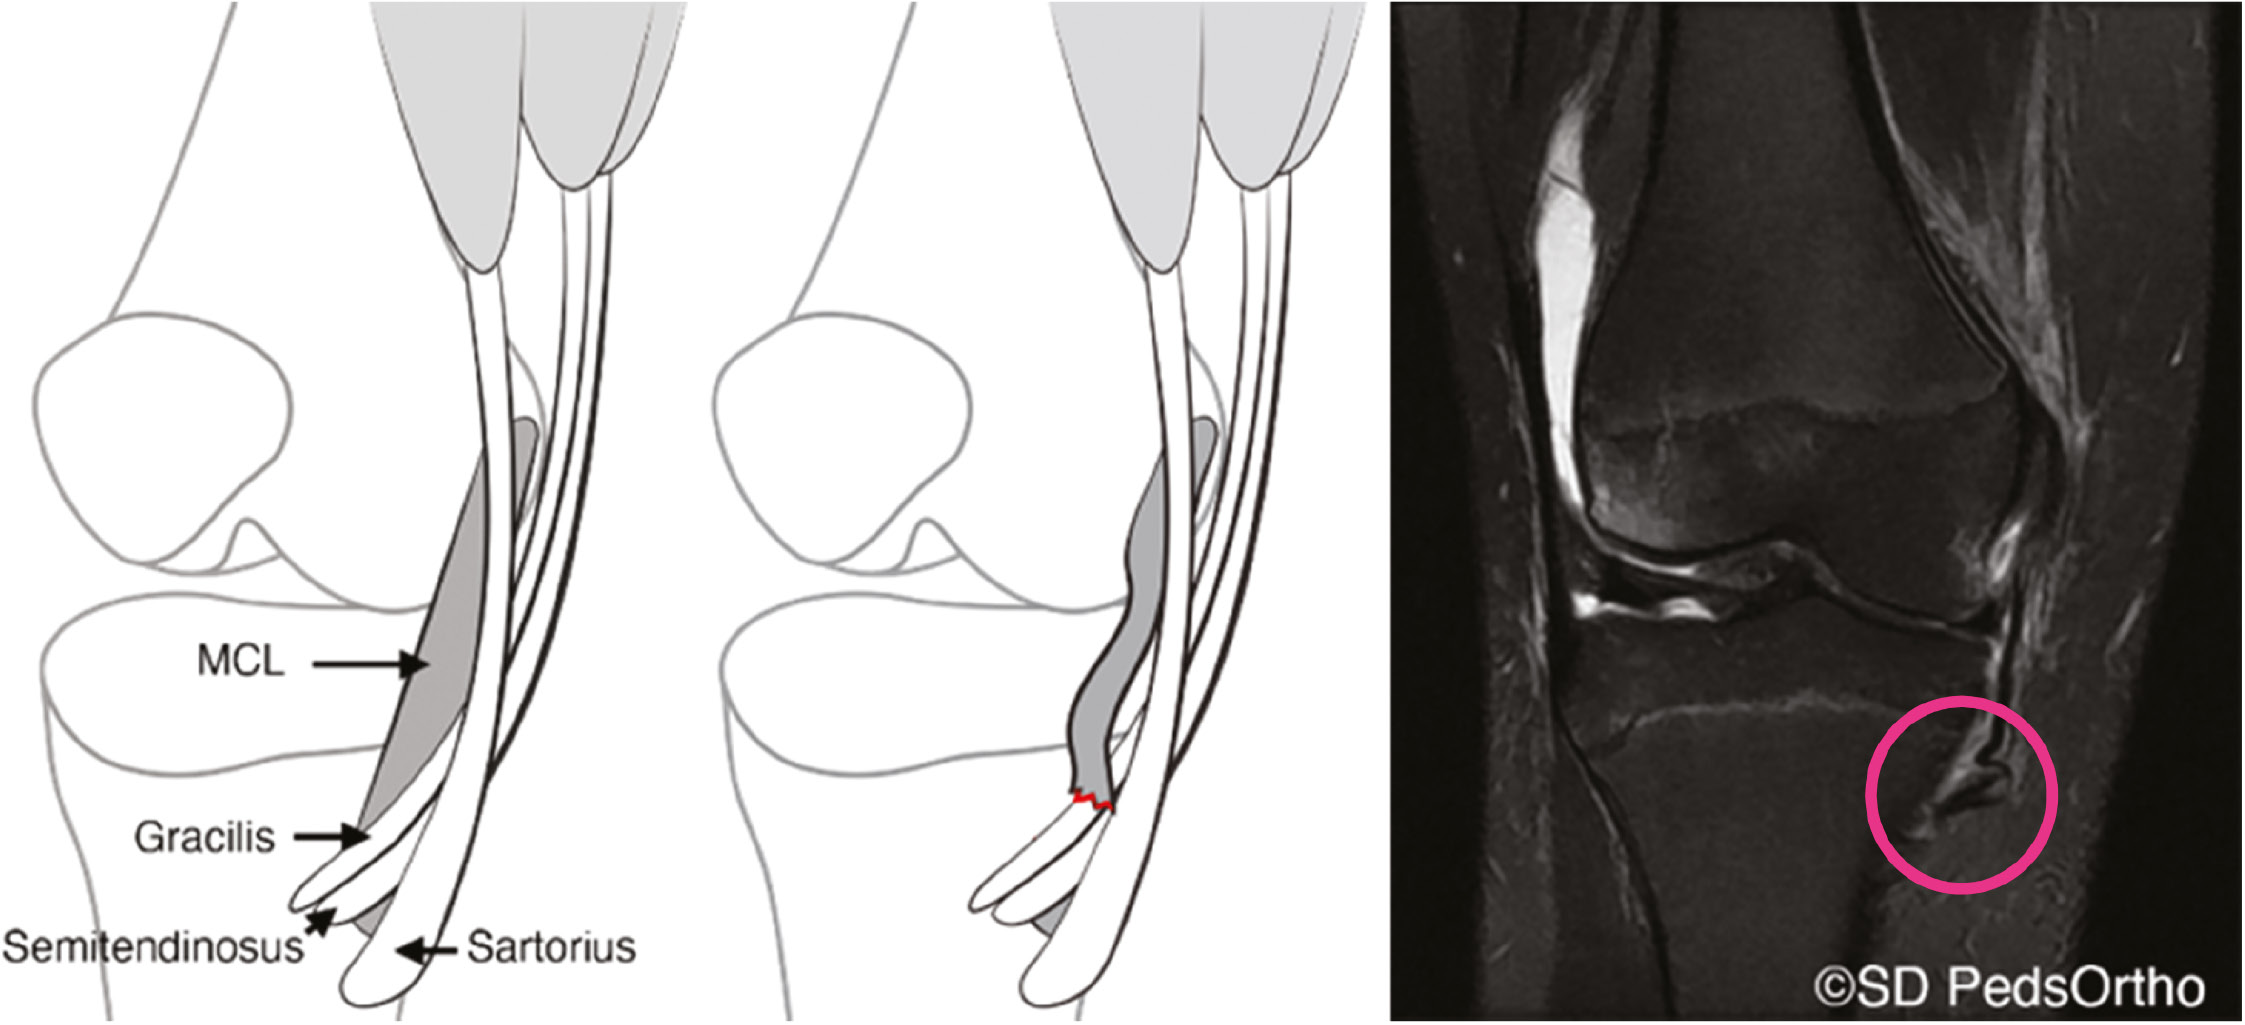

Magnetic Resonance Imaging

In cases where significant medial instability is encountered on exam or with stress radiographs, an MRI is indicated to assess the extent of the medial-sided injury as well as to evaluate the bone, menisci, cartilage, and surrounding ligamentous structures. Furthermore, if an effusion is encountered on examination, an MRI is indicated to better assess a concomitant intra-articular injury. Once obtained, the medial structures should be individually scrutinized including the dMCL, the sMCL, and the underlying meniscus. This will give a better sense of the extent of the injury as well as the healing potential (Figure 9). Distal ruptures of the superficial MCL injury with the ligament flipped over the pes tendons (Stener-like lesion) likely have the worst healing potential and may require surgical intervention (Figure 10).18

Figure 10. Stener-like lesion (pink circle) of the distal MCL with the superficial MCL avulsed from the tibia and flipped over the pes tendons.